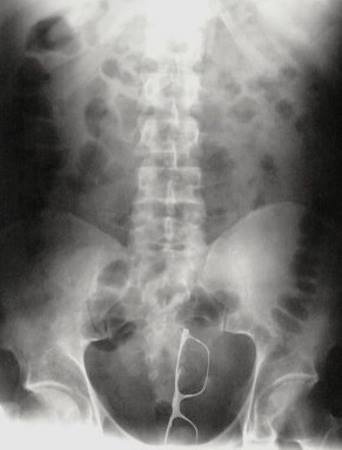

Óculos:

Já imaginou encontrar um óculos de armação grossa dentro de você? A dúvida que resta é, seria um óculos de sol ou de grau? Que horror!!!